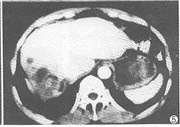

例1 男,60岁。反复发作性右上腹痛半年余。CT示肝左叶增大,右叶缩小,右叶背段见大片混杂密度区,边界欠清;增强后强化不明显,其内见斑点状及长条状结石影,左肝管及胆总管下端亦呈高密度铸形(图1),胆囊位于肝右叶后方(图2)。术后病理:(1)肝右叶胆管细胞癌;(2)肝内胆管及胆总管结石;(3)肝右叶后胆囊。

图2 肝右叶后方见椭圆形低密度影,密度均匀,壁光整